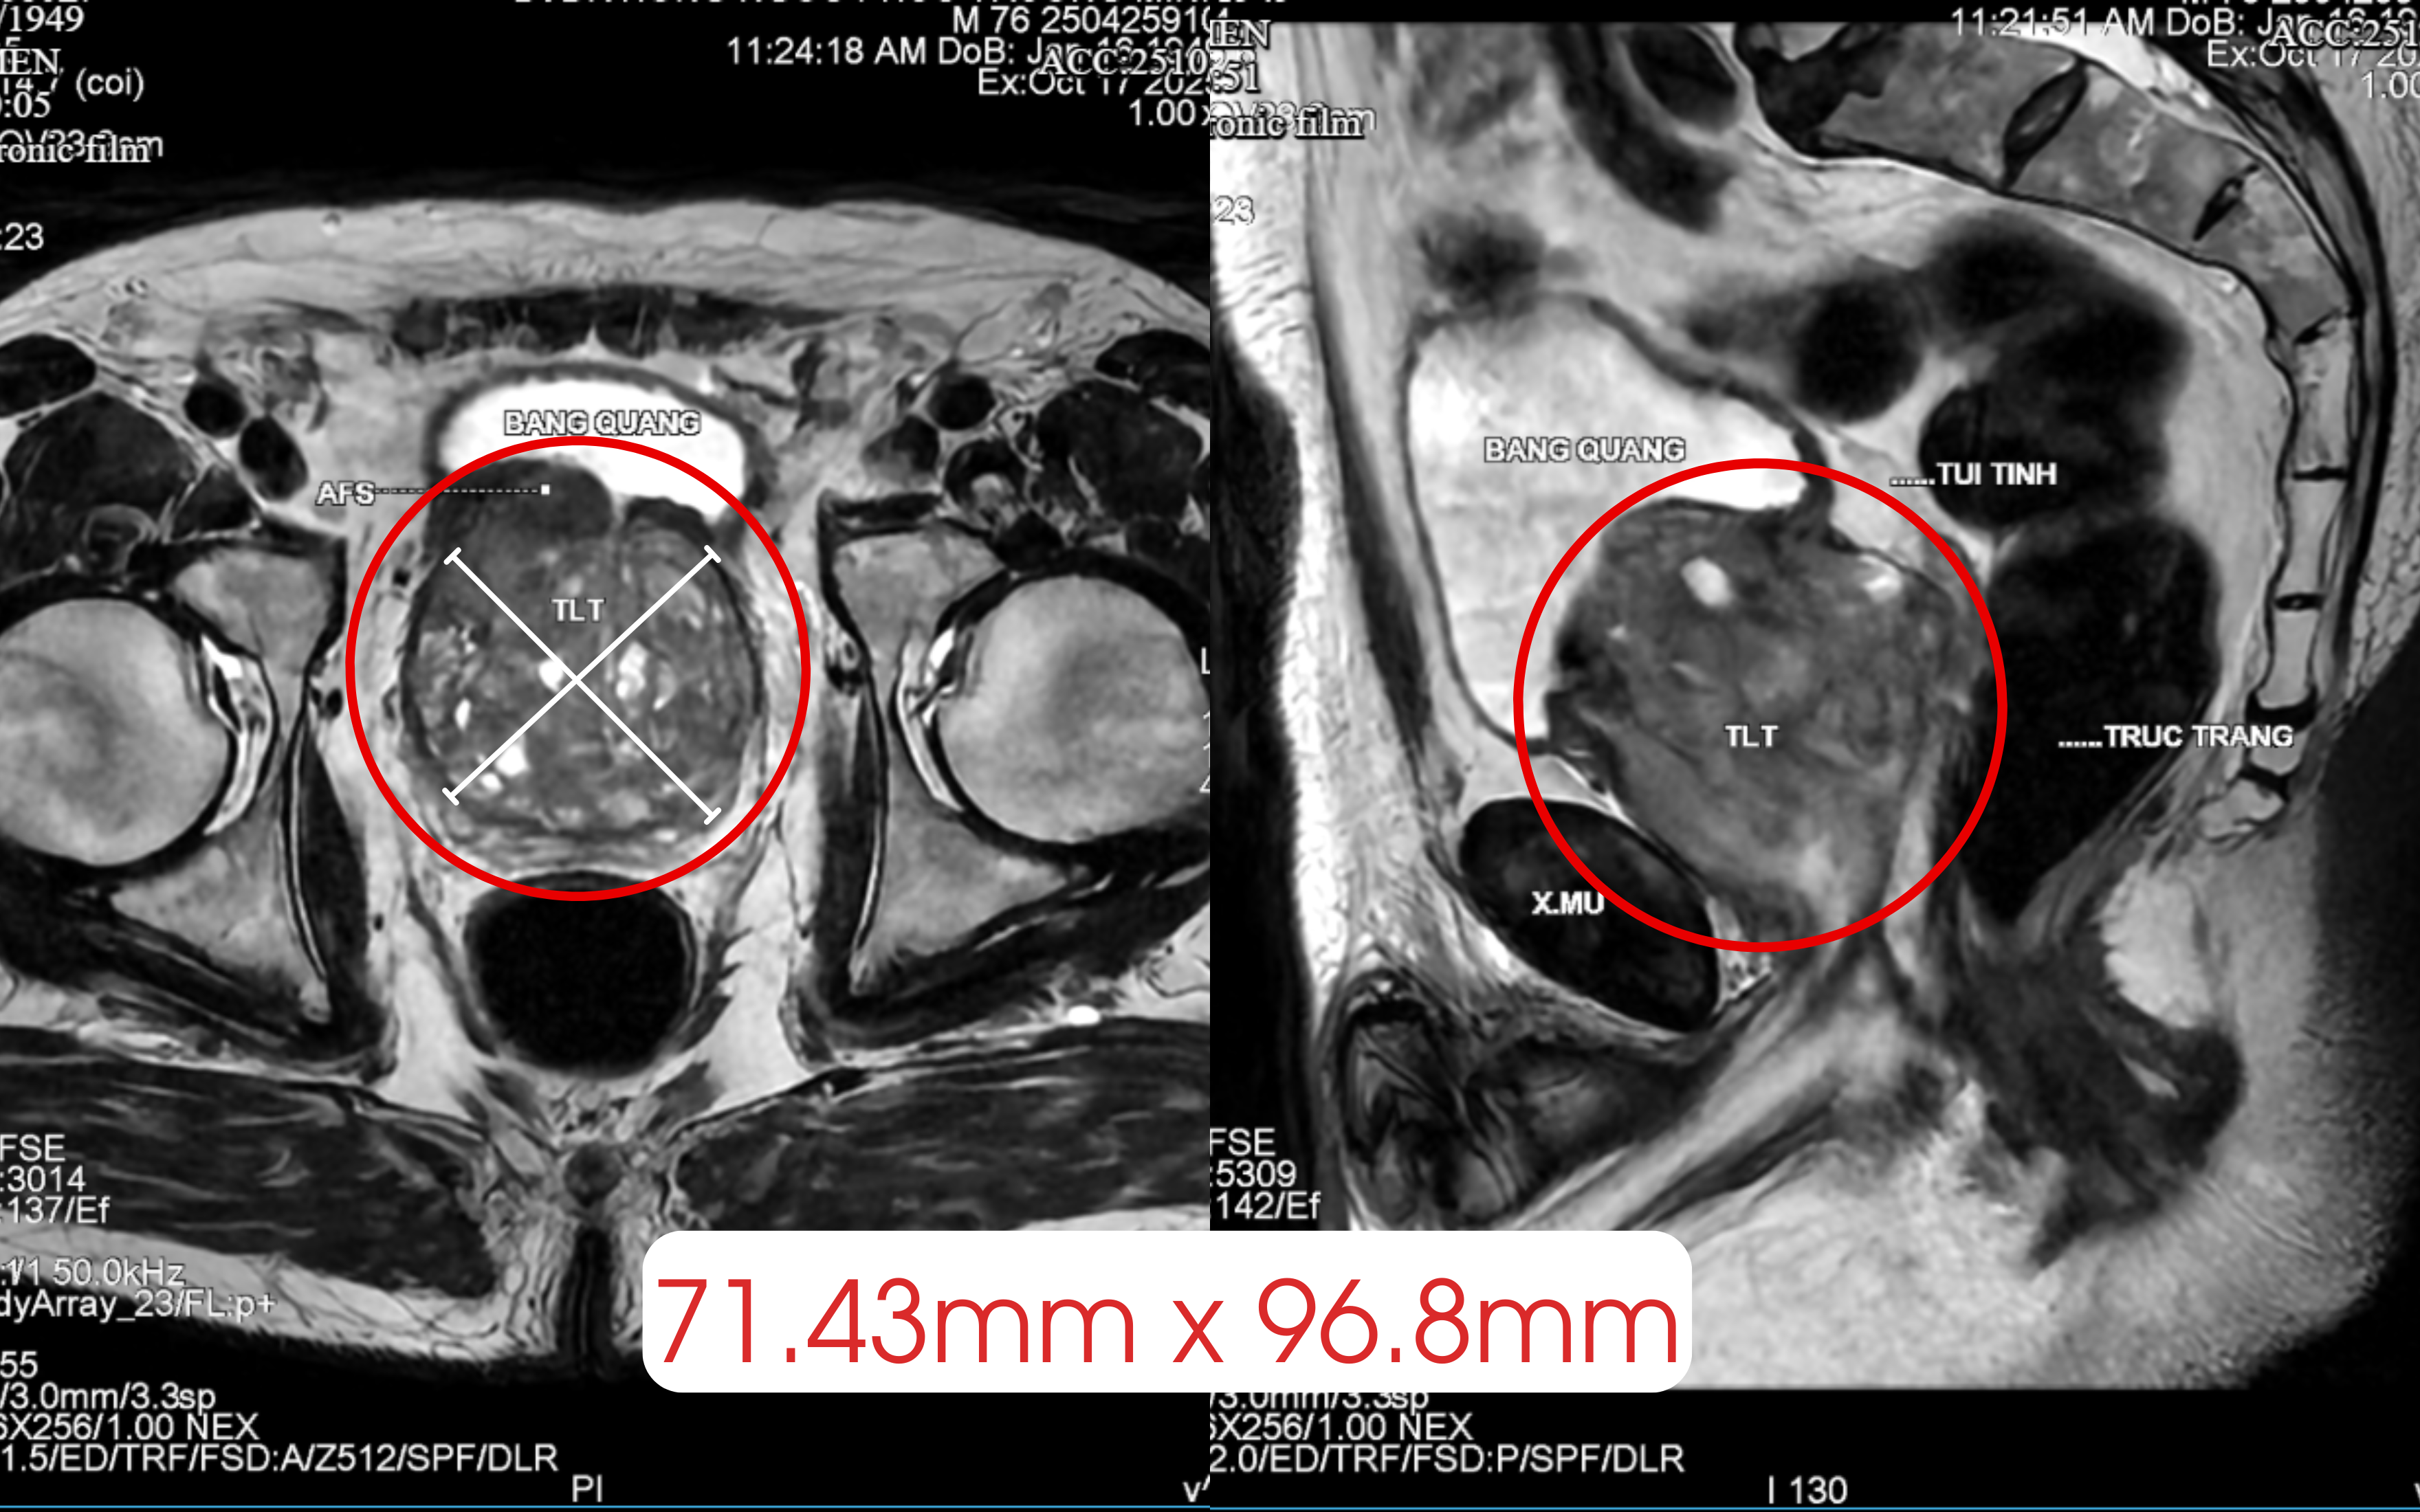

병원 도착 후 시행한 CT 촬영 결과, 그의 전립선 무게는 정상 수치(20~25g)의 10배인 245g에 달했습니다. 거대해진 전립선이 방광을 심하게 압박하여 방광 용적을 줄이고 지속적인 자극을 유발했던 것입니다. 이는 기존의 약물 치료가 효과가 없었던 근본적인 원인이었습니다.

CT 영상에 나타난 거대 전립선 이미지